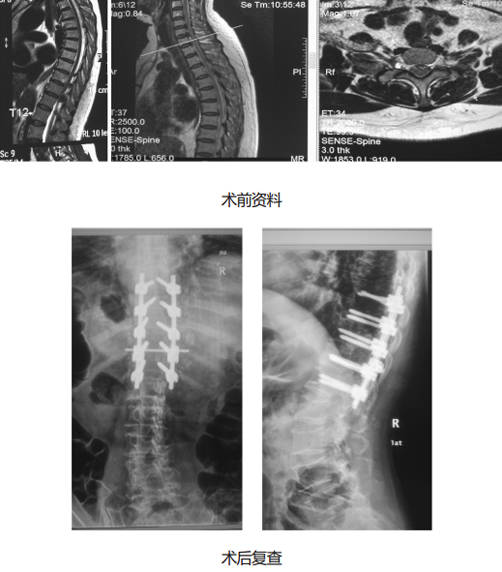

对于胸椎后凸畸形、脊髓受压严重、多节段胸椎管狭窄等复杂的胸椎管狭窄症的患者,可以进行手术治疗。手术治疗在胸椎后方对胸椎管进行扩大,直接解除对脊髓的压迫,神经减压充分。

技术优势:1.减压范围更大,椎管容积变大,脊髓的空间更大, 2.对合并胸椎畸形的患者,可以进行减压的同时,给予畸形矫正。

适应证:胸椎后凸畸形、脊髓受压严重、多节段胸椎管狭窄等复杂的胸椎管狭窄症